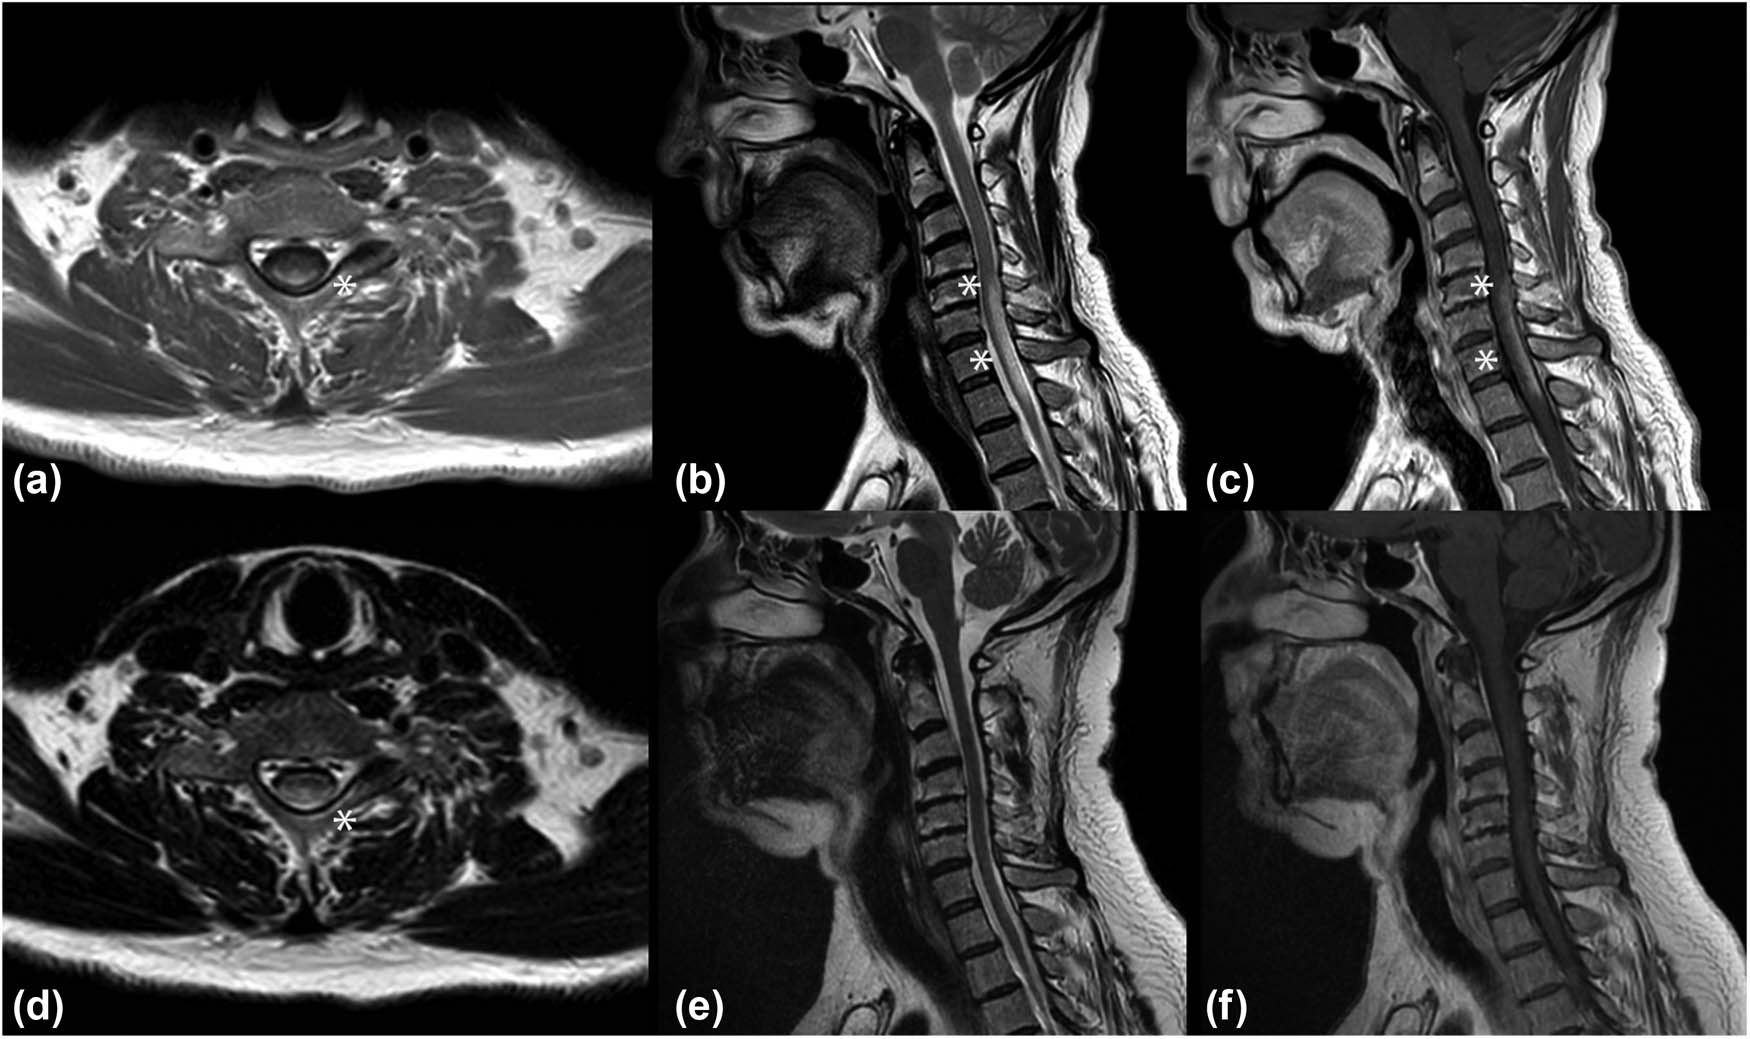

Cerebrospinal fluid (CSF) analysis showed mildly elevated protein level (48 mg/dL) with normal glycorrhachia and no cells. Oligoclonal bands were absent. Anti-AQP4 and anti-MOG antibodies in serum, tested through a cell-based assay (CBC), were not detected. To exclude paraneoplastic etiology, a total body computed tomography (CT) was performed. Despite the complete absence of respiratory symptoms, the thoracic CT scan showed multiple enlarged lymph nodes with central colliquation in mediastinal and hilar stations (Figure 2). The histological analysis conducted on the transbronchial needle biopsy demonstrated granulomatous lymphadenitis with non-caseating granulomas supportive for the diagnosis of sarcoidosis. Based on the criteria proposed by Zajicek et al., our patient fitted the criteria of probable neurosarcoidosis (NS) [3].

Axial chest CT scan showing bilateral hilar adenopathy (asterisks).

The patient was treated with high doses of intravenous corticosteroid therapy for 5 days (methylprednisolone 1 g per day) and after discharge with tapering doses of oral corticosteroids starting from prednisone 50 mg per day with slow reduction until suspension after 9 months. A new MRI of the cervical and dorsal spine was performed 6 weeks later showing the almost complete disappearance of the inflammatory lesion and the absence of contrast enhancement (Figure 1). Mycophenolate mofetil was added 3 months later. A thoracic CT scan performed 1 year later showed the reduction in the mediastinal and hilar lymph nodes. No clinical or radiological relapses were reported in the two following years.